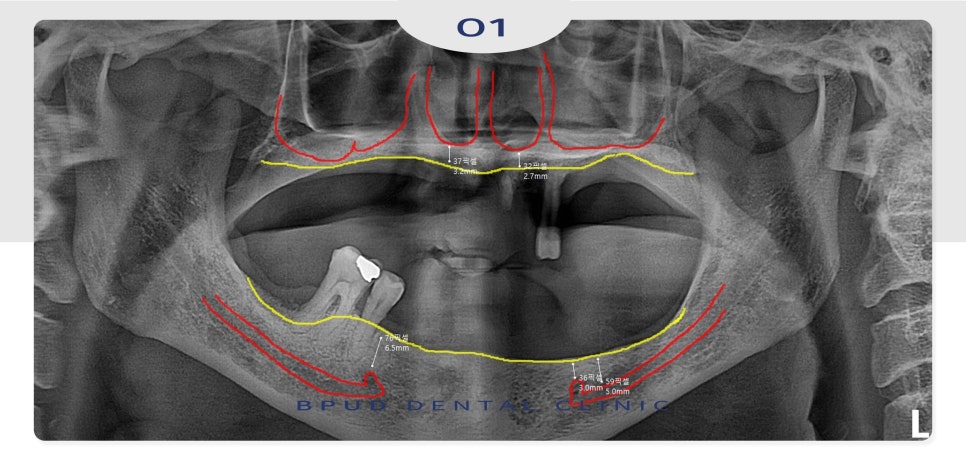

임상 검사로 CT 촬영 시,

골흡수가 심하게 진행된 상태였는데요.

전체 임플란트가 진행되어야 하는 상황이지만

위쪽의 골흡수가 더 심하여 현재의 상태로

보철물이 제작된다면 심미적이지 않은 상태로

제작될 가능성이 높을 것으로 판단되었습니다.

옆에서 보았을 때와 위쪽 뼈를 본

CT인데요.